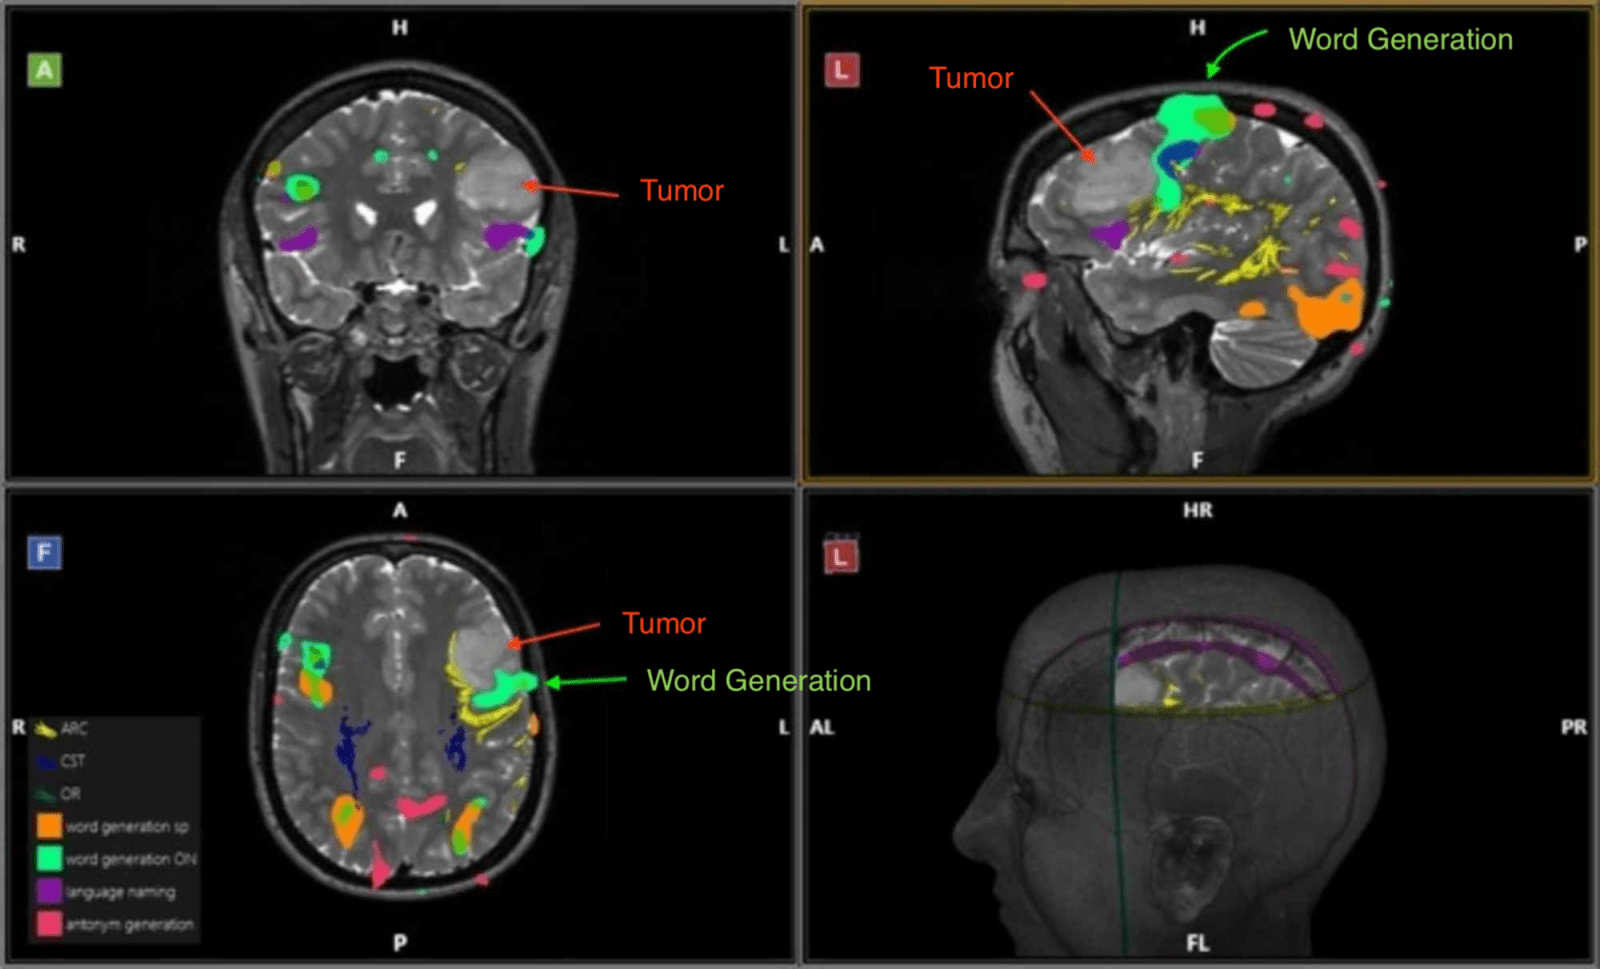

تصویربرداری FMRI

تصویربرداری تشدید مغناطیسی عملکردی (تصویربرداری fMRI) تغییرات جزئی در جریان خون را که با فعالیت مغز اتفاق می افتد اندازه گیری می کند. ممکن است برای بررسی آناتومی عملکردی مغز (تعیین اینکه کدام قسمت از مغز عملکردهای مهم را انجام می دهند) ، ارزیابی اثرات سکته مغزی یا راهنمایی درمان مغز استفاده شود. تصویربرداری fMRI ممکن است ناهنجاری هایی را در مغز تشخیص دهد که با سایر روش های تصویربرداری یافت نمی شود. تصویربرداری fMRI در حال تبدیل شدن به

آنالیز FMRI

پس از طراحی پارادایم fMRI و اجرای آزمایش و جمع آوری داده ها ، قبل از اینکه دانشمندان علوم مغز و اعصاب و پزشکان بتوانند به سوالات مربوط به فعالیت های مربوط به آزمایش دست یابند ، باید مراحل مختلف آنالیز fMRI را بر روی داده های حاصل شده اعمال کرد. هدف از آنالیز مبتنی بر رایانه ، تعیین خودکار آن قسمت هایی از مغز است که به محرک هایی که به افراد ارائه می شود پاسخ می دهند. روشهای